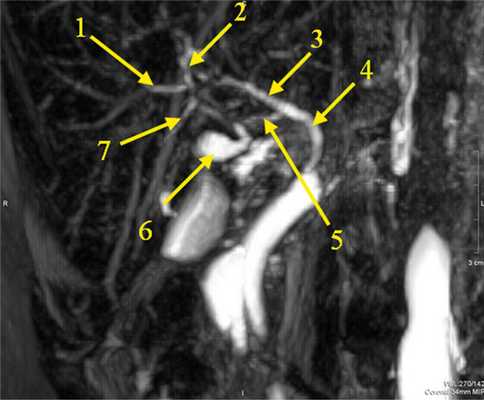

По данным магнитно-резонансной томографии, холангиографии (рис. 2): печень в размере не увеличена, контуры ровные, четкие, структура однородная, без очаговых образований. Внутри- и внепеченочные желчные протоки не расширены. Внутрипеченочные сосуды не изменены. Желчный пузырь нормальных размеров — 3,3×1,5 см, имеется перегиб ближе к шейке, содержимое однородное. Стенки пузыря тонкие. Гепатикохоледох визуализируется на всем протяжении, имеет равномерный просвет диаметром 4 мм. Визуализируется бифуркация желчевыводящих путей на правый и левый долевые протоки диаметром 2 мм, имеется дополнительный правый долевой проток диаметром 2 мм, сегментарные протоки не визуализируются. Отчетливо определяется пузырный проток 1,5 мм в диаметре (см. рис. 2). Патологии органов брюшной полости и забрюшинного пространства не выявлено.

Рис. 2. Магнитно-резонансная холангиография. 1 — правый долевой желчный проток; 2 — левый долевой желчный проток; 3 — общий печеночный желчный проток; 4 — общий желчный проток; 5 — пузырный проток; 6 — желчный пузырь; 7 — дополнительный правый желчный проток.